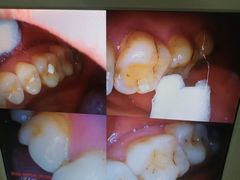

• 土豆口腔(凤凰北总店)

• -土豆口腔(凤凰北总店)